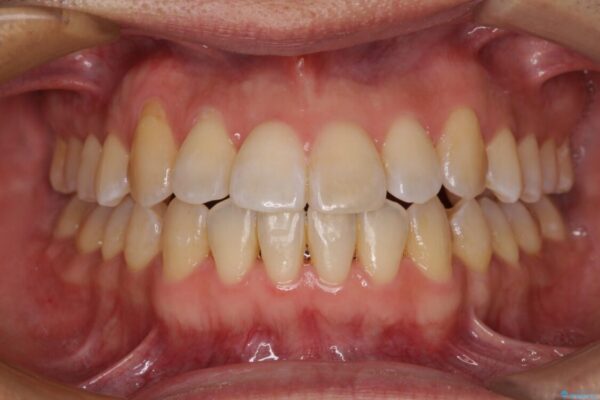

治療前

• 左右の八重歯が気になる ワイヤー装置での咬み合わせ改善 治療前画像